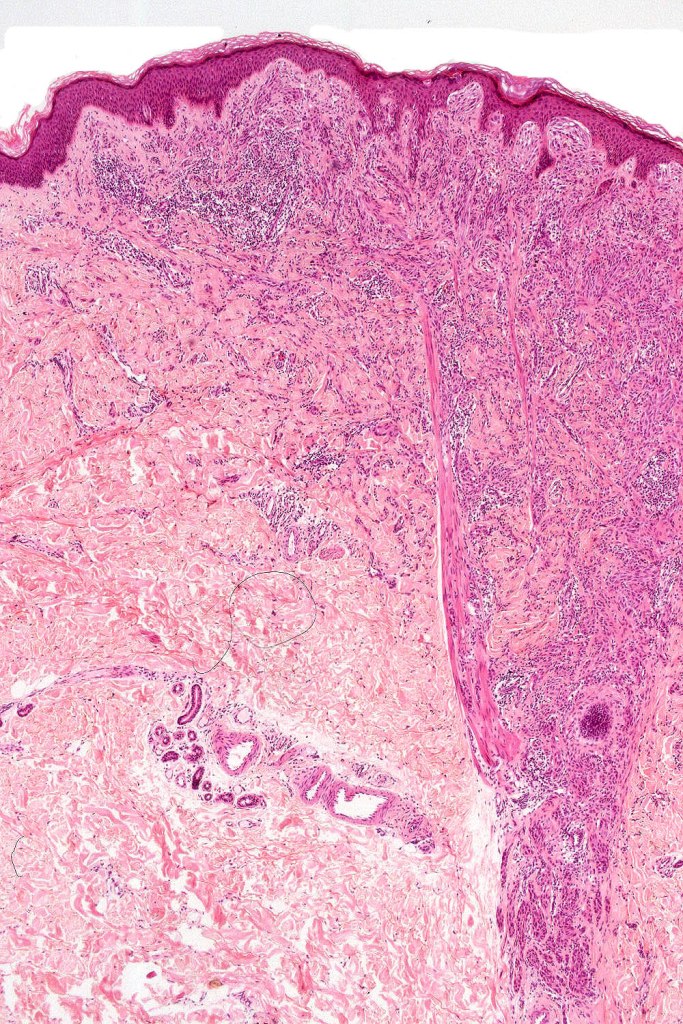

•Sharply circumscribed (begins and ends with a nest), symmetrical dome-shaped lesion. Symmetry is both horizontal and vertical (see image below)

•Wedge-shaped with the base uppermost or sometimes plaque-shaped silhouette

•Superficial vascular ectasia very frequently present

•Junctional nests often vertically orientated, dyscohesive with a surrounding retraction artifact

•Lymphocytic infiltration at the base of the lesion